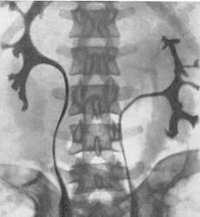

• Внутривенная пиелография:

о Срединное сращение:

- Чашечки как бы «держатся за руки»: нижние чашечки спускаются к средней линии около перешейка

- U-образная нефрограмма

- Редко чашечки от противоположных почек соединяются, образуя общую почечную лоханку с одним мочеточником

о Боковое сращение:

- Нижние чашечки пересекают среднюю линию и дренируют часть паренхимы противоположной почки

- L-образная нефрограмма

- Одна часть пересекает среднюю линию и располагается в поперечном положении, почечная лоханка лежит спереди или латерально

- Оставшаяся часть находится в вертикальном положении, почечная лоханка лежит спереди или медиально

о Большие и экстраренальные лоханки почки:

- Почечные лоханки, как правило, большие и дряблые; место отхождения мочеточников от почечных лоханок расположено аномально высоко

о Симптом «цветочной вазы»: каждый мочеточник пересекает перешеек, изгибается латерально и продолжается медиально (при нормальным ходе-дистально)

о От почек отходят раздвоенные или двойные мочеточники